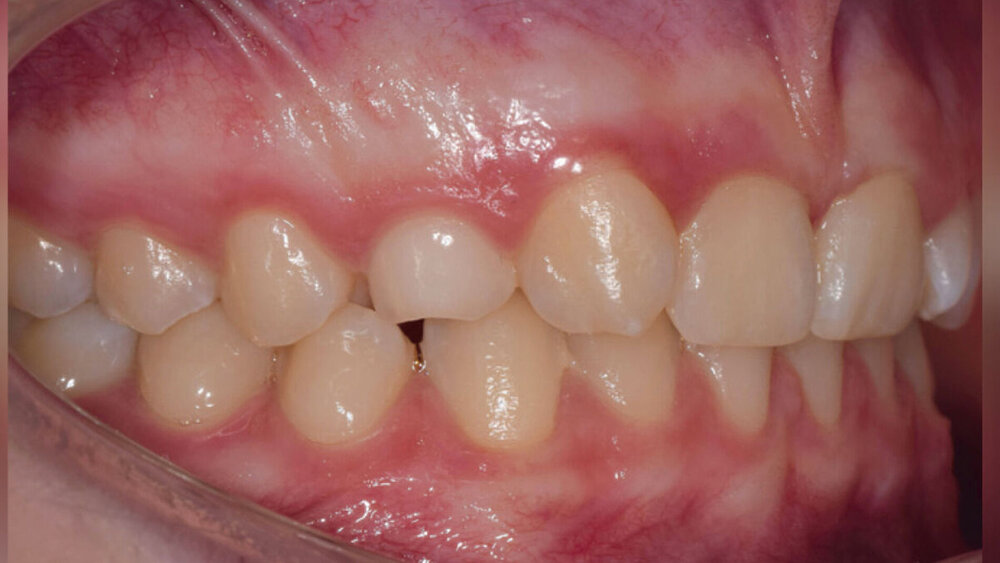

Die 14-jährige Patientin stellte sich bei unauffälliger Allgemeinanamnese in der Poliklinik für Kieferorthopädie der Universitätsmedizin der Johannes-Gutenberg-Universität in Mainz nach Überweisung durch den Hauszahnarzt vor. Die Anamnese ergab die Nichtanlage des Zahnes 12 bei Milchzahnpersistenz von 53, Durchbruch von 13 in Regio 12 (Abbildung 2b), Hypoplasie des 22 sowie den Verdacht auf einen retralen Zwangsbiss. Des Weiteren imponierte in beiden Kiefern ein frontaler Engstand mit retrudiert-stehender Front bei normal großen Kieferbasen (Abbildung 1). Durch Aufwanderung der Seitenzähne im Oberkiefer kam es zu einer distalen Verzahnung beidseits bei einer skelettalen Neutralbisslage mit progener Tendenz (Abbildung 2a).

Die Patientin störten am eigenen Lächeln die disharmonischen Zahnformen und die Schachtelstellung in der Oberkieferfront (Abbildung 1b). Neben der Harmonisierung des sichtbaren Lächelns war ihr Wunsch eine mitarbeitsunabhängige und zügige Therapie, bei einer wenig sichtbaren Behandlungsapparatur und einem vorhersagbaren Behandlungsergebnis ohne weitere Maßnahmen im jungen Erwachsenenalter.

Nach der gesicherten Diagnose einer Aplasie spielen neben der Anzahl fehlender Zähne eine Reihe weiterer Parameter eine entscheidende Rolle für die Therapieplanung. Wie das Patientenbeispiel mit einer unilateralen Nichtanlage eines seitlichen Schneidezahns zeigt (Abbildungen 1 und 2), müssen dabei neben der Form, der Farbe und der Durchbruchsposition des bleibenden Eckzahns [Brough et al., 2010] das dentale und das chronologische Alter, der Wachstums- und Profiltyp, die Okklusion, die Mundhygiene und die Compliance des Patienten berücksichtigt werden. Grundsätzlich muss hier eine Therapieentscheidung zwischen Lückenschluss oder Lückenöffnung getroffen werden. Der Patient ist dabei vorab über alle möglichen Behandlungsalternativen, deren Vor- und Nachteile sowie die Risiken aufzuklären und in die Entscheidung einzubeziehen.

Der ästhetischen Weiterversorgung des Patienten bei einem geplanten Lückenschluss im Frontzahnbereich muss besondere Aufmerksamkeit geschenkt werden. Hier ist es ratsam, dass der Kieferorthopäde und der Zahnarzt sich frühzeitig austauschen, um ein ästhetisches Gesamtkonzept festzulegen. Gerade bei der Nichtanlage von Zähnen sind mögliche Mikrosymptome zu berücksichtigen, wie bei der Aplasie eines seitlichen Schneidezahns die Hypoplasie des gegenüberliegenden seitlichen Schneidezahns (Abbildungen 1b und 1c).